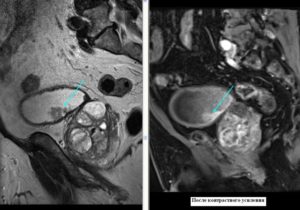

Визуализируется экзофитно растущее в просвет мочевого пузыря объемное образование на ножке (папиллярная уротелиальная опухоль).

С целью оценки глубины инвазии опухоли в стенку мочевого пузыря при МРТ исследовании используется внутривенное динамическое контрастирование.

Неинвазивная папиллярная уротелиальная опухоль. Корональное Т2-взвешенное МР- изображение показывает тканевой интенсивности сигнала опухоль (стрелка),растущая в просвет мочевойго пузыря.

При бесконтрастном исследовании создается впечатление о сохранности прилежащих отделов гипоинтенсивной стенки мочевого пузыря.

Однако достоверно судить о степени глубины инвазии можно только по постконтрастным сканам.

При этом важно проведение именно динамического внутривенного контрастирования (в артериальную фазу происходит усиление только ткани опухоли, но еще не успевает произойти усиление интактной стенки мочевого пузыря). На представленном контрастном Т1-ВИ изображении (артериальная фаза) на фоне накопления КВ тканью опухоли, подслизистого слоя, видно отсутствие инвазии прилежащей стенки мочевого пузыря.